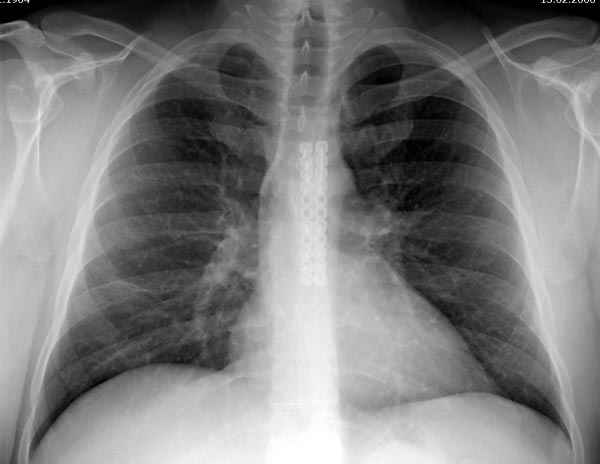

Оперировали вместе с грудным хирургом и в нашем случае главной причиной была болезненность. Во время операции приняли все меры предосторожности недопущения прокола средостения (см. на 4 снимке близкий контур сердца!!)

Рентген снимки во время операции и последние сделаны на днях.